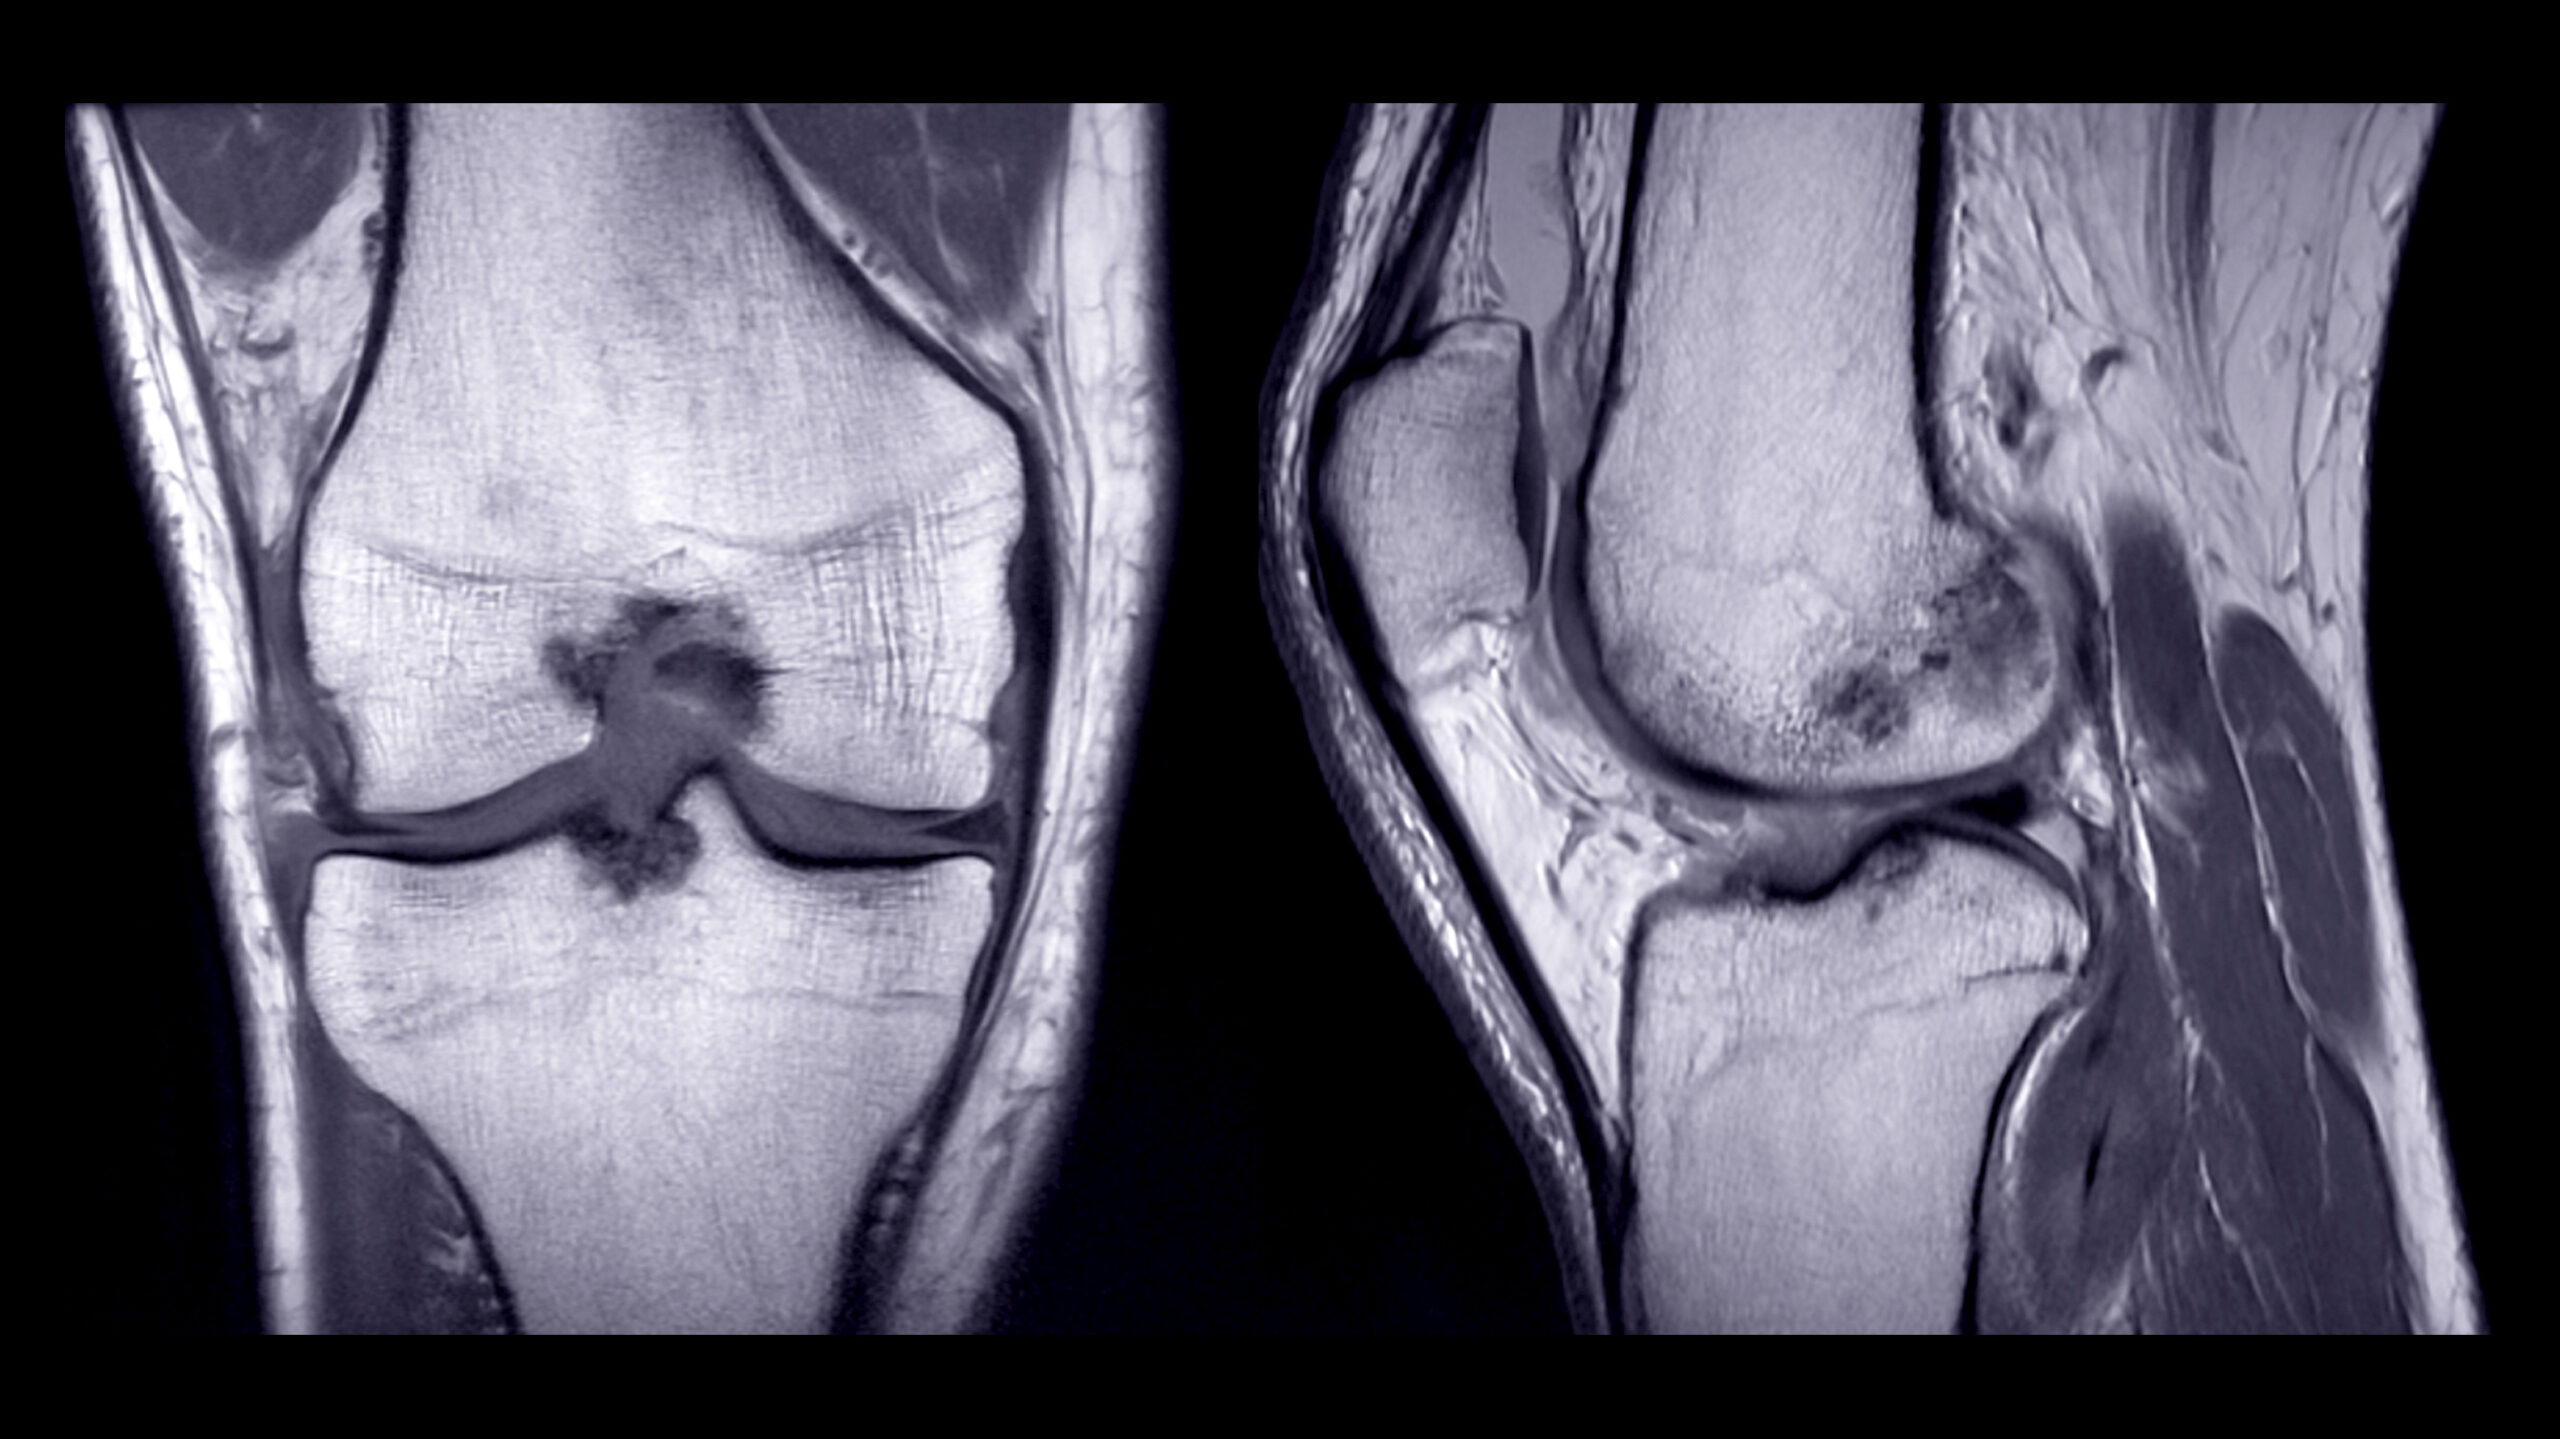

A knee MRI uses a powerful magnetic field and radio waves to create detailed images of the tissues inside your knee. Unlike X-rays, which are more effective for viewing bones, an MRI excels in showing soft tissues like cartilage, ligaments, tendons, and muscles. This makes it an invaluable tool for diagnosing a wide range of knee conditions that might not be visible through other imaging methods.

- Meniscus Tears: The meniscus is a wedge-shaped cartilage that acts as a cushion between your thighbone and shinbone. An MRI can reveal tears in the meniscus, which may appear as a change in its shape or position.

- Ligament Injuries: The knee contains several crucial ligaments, including the anterior cruciate ligament (ACL) and posterior cruciate ligament (PCL). An MRI can detect tears or sprains in these ligaments, which are common in athletes and active individuals.

- Cartilage Damage: Cartilage provides a smooth surface for bones to glide over each other in the joint. Damage to cartilage can lead to conditions like osteoarthritis, which can be visualized with an MRI.

- Fluid Build-Up: The presence of excess fluid in the knee joint, often due to inflammation or injury, can be detected on an MRI as bright white areas.

The meniscus plays a vital role in knee stability and shock absorption. When it’s damaged, it can lead to pain, swelling, and difficulty moving the knee. On an MRI, a meniscus tear might appear as a disruption or abnormal shape in the cartilage. Common types of meniscus tears include:

- ACL Tears: Often seen in conjunction with a bone bruise, an ACL tear on an MRI may appear as a disruption or a lack of continuity in the ligament fibers.

Cartilage degradation is a common issue as we age, and it’s a primary factor in conditions like osteoarthritis. An MRI can show:

- Cartilage Loss: Reduced cartilage thickness or roughened surfaces, indicative of wear and tear.

Fluid in the knee joint can be a sign of inflammation or injury. On an MRI, fluid build-up is typically seen as bright white areas within the joint. This could be due to: